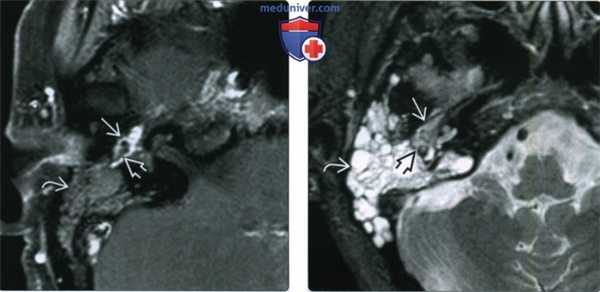

(Слева) При аксиальной МРТ Т1 ВИ С+ FS правой височной кости определяется контрастирующаяся ГТП, заполняющая среднее ухо. Обратите внимание на гипоинтенсивные слуховые косточки, погруженные в опухоль. Определяется обструкция входа в пещеру, приводящая к появлению неконтрастирующейся жидкости в ячейках сосцевидного отростка.

(Справа) При аксиальной MPT Т2 FS в среднем ухе определяется гломусная опухоль с промежуточной интенсивностью сигнала по сравнению с гиперинтенсивным содержимым в сосцевидном отростке. Обратите внимание, что задний край опухоли приводит к обструкции входа в пещеру.